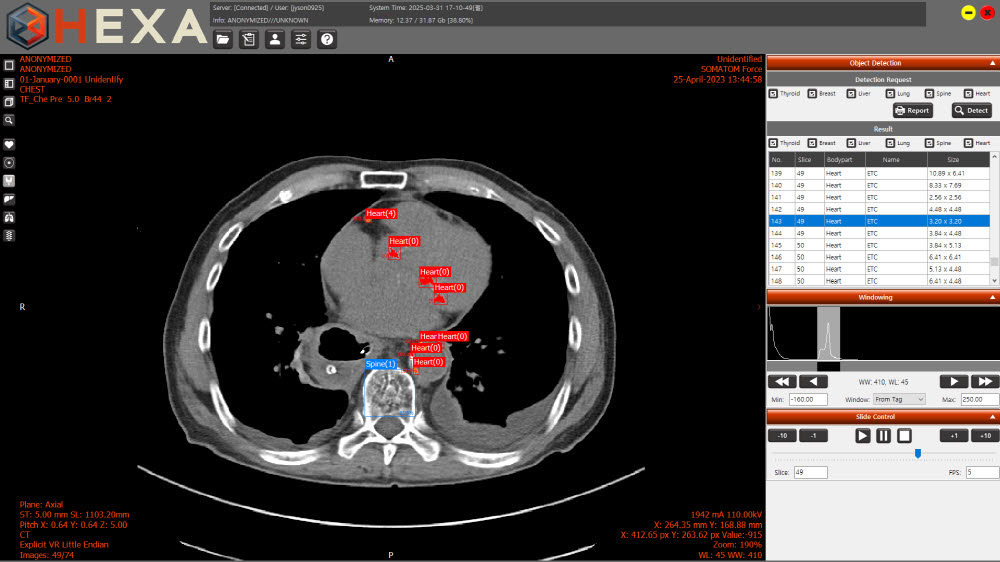

헬스테크 기업 ㈜엑스큐브가 흉부 CT 기반 다장기 인공지능(AI) 진단보조 소프트웨어 ‘HEXA(헥사)’를 정식 출시했다. HEXA는 한 번의 흉부 CT 촬영으로 갑상선, 심장, 폐, 간, 유방, 척추 등 6개 장기의 이상 소견을 AI가 자동 표시해주는 솔루션이다. 기존 주된 질환 위주 판독 과정에서 놓칠 수 있었던 다른 장기의 이상 소견 누락 가능성을 줄이는 데 초점을 맞춰 개발됐다. 서울바이오허브의 ‘병원기반 의료데이터 활용 지원사업’에 참여해 실제 임상 환경 기반 연구를 수행하며 기능을 고도화한 결과로, 현재 다수 의료기관에서 실제 판독 환경에 적용되고 있다. 엑스큐브는 HEXA가 바쁜 진료 환경에서 이상 소견을 한 번 더 확인하는 ‘안전망’ 역할을 수행할 수 있도록 국내 적용을 확대하고, 인도네시아 등 해외 시장 진출을 병행할 계획이라고 밝혔다.